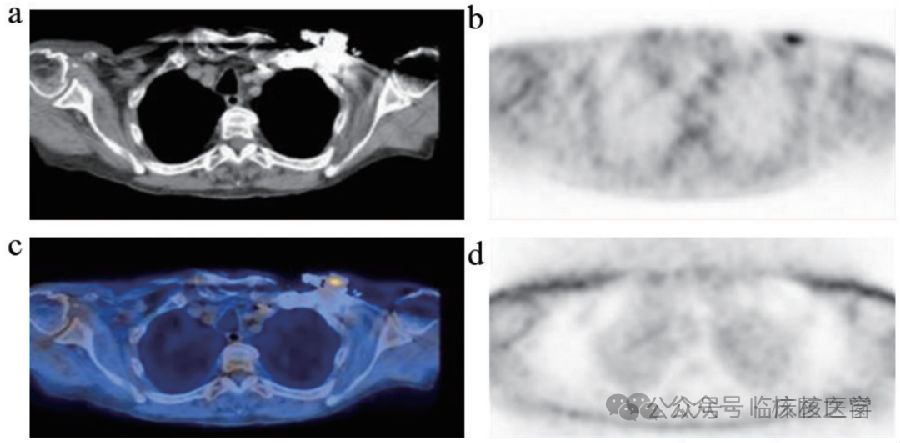

体内心脏起搏器导致的伪影

a.CT图像;b.经CT衰减校正的PET图像;

c.CT融合图像;d.未经CT衰减校正的图像

(病例来源:陈蕾蕾,陈自谦,许尚文,肖慧,钟群,付丽媛,钱根年.PET/CT显像常见伪影及质量控制[J]中国医疗设备.2019.34(02):17-24.)